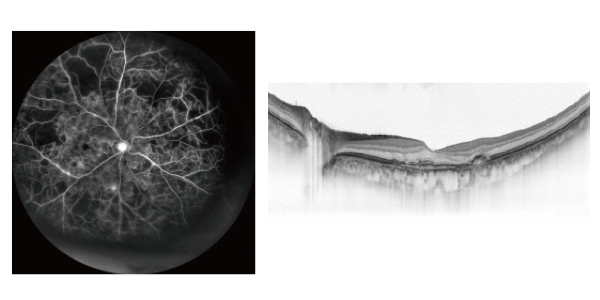

ミランテ

特長

・眼底マルチモダルイメージング

・4Kの高解像度な広角*1・カラーSLO

・16.5×12mmの広範囲OCT撮影

・長眼軸長正常眼データベース*1を搭載可能

・OCT-Angiography*1による診断サポート

・Bスキャンデノイジングソフトウェア*1を搭載可能

当院ではニデック社の最上位機種であるミランテを導入しております。ミランテは従来の眼底カメラに比べてかなり眼底の広い範囲を撮影可能であり、電子カルテと組み合わせることにより、今までは眼科医しか見れていなかった眼底の端の病変も患者様に診察室で見て頂くことが可能です。

またこの器械一台で、広角カメラ、OCT,OCTアンギオ、FAG、の検査が出来る優れものです。

検査の時に場所を移動する必要は無く、またOCTアンギオは点滴注射をして、今までのFAG検査で必要だった造影剤を体内に入れる負担のある検査が必要なくなりました。そのため、糖尿病網膜症や網膜中心静脈分岐閉塞症における無灌流領域の場所がすぐに分かり、治療につなげることができます。

もちろんOCT(網膜の断層図)もとてもきれいに撮影できます。